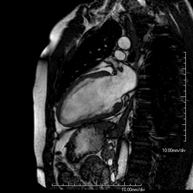

És una prova diagnòstica no invasiva que obté informació morfològica i funcional del cor i les estructures adjacents. D'aquesta manera es poden diagnosticar diferents patologies congènites i adquirides i realitzar controls en pacients amb patologia prèvia ja coneguda. En la majoria de casos és necessari l'ús de contrast intravenós (Gadolini) per completar l'estudi, un tipus de contrast que estranyament produeix reaccions adverses. Durant la prova el tècnic li demanarà diverses vegades que aguanti la respiració durant 10-15 segons per obtenir les imatges el més clares possible. No requereix preparació prèvia per part del pacient. La durada de la prova és d'aproximadament 45-60 minuts. Està contraindicada en pacients amb marcapassos i el pacient ha d'indicar si és portador d'implants metàl·lics i/o clips quirúrgics. - RM Cardíaca amb estrès miocàrdic

És una prova diagnòstica no invasiva que obté informació morfològica i funcional del cor i les estructures adjacents. D'aquesta manera es poden diagnosticar diferents patologies congènites i adquirides. Durant la prova el tècnic li demanarà diverses vegades que aguanti la respiració durant 10-15 segons per poder obtenir les imatges el més clares possible. En la gran majoria de casos és necessari l'ús de contrast intravenós (Gadolini) per completar l'estudi, un tipus de contrast que rarament produeix reaccions adverses. A més, s'introdueix un fàrmac (Adenosina) per via intravenosa, per exercir sobre el cor un efecte similar al que es produeix durant l'exercici físic. Es comparen les imatges obtingudes en repòs i després de "l'estrès" farmacològic per detectar dèficits d'aportació sanguini al ventricle esquerre del cor. La durada de la prova és d'aproximadament 45-60 minuts. El pacient no haurà d'ingerir aliments que continguin cafeïna durant les 24 hores prèvies a prova (cafè, te, xocolata, begudes de cola, etc.). Està contraindicada en pacients amb marcapassos i el pacient ha d'avisar si és portador d'implants metàl·lics i/o clips quirúrgics. - Angio-RM de Venes pulmonars